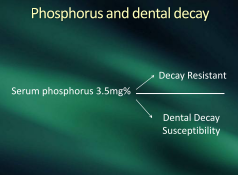

Add Page’s phosphorus of 3.5

Now we can let a tooth survive

Dental decay is not endemic

the problem here is totally systemic

Food’s more effective than the brush

hard foods better than softened mush

Watch your chemistry for the 3 point 5

and that will keep your teeth alive